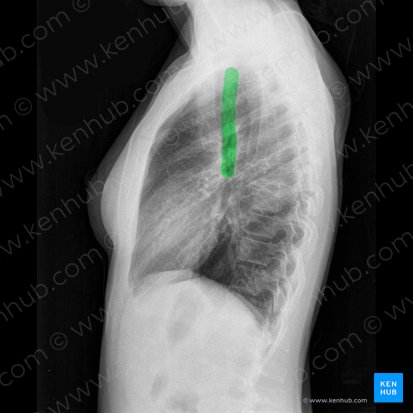

Penetration (Belichtung des Röntgenbildes)

Die Penetration (Bеlichtung) beschreibt die Strahlenmenge, welche sich aus Strahlenenergie und Strahlenintensität ergibt. Sie wirkt während der Aufnahme auf den darzustellenden Körper ein und sorgt im Idealfall für eine Röntgenaufnahme mit deutlich erkennbaren Strukturen. Bei einer optimal belichteten Aufnahme sind die Wirbelkörper hinter dem Herzen kaum zu sehen und das Zwerchfell kann bis zum Rand der Wirbelsäule nachverfolgt werden.

Ebenso wichtig ist die Betrachtung der Luftröhre (Trachea): Normalerweise sollte sie mittig liegen. Sollte das nicht der Fall sein, suche nach Fremdkörpern in den Bronchien, einer Mittellinienverlagerung anderer mediastinaler Strukturen oder Anzeichen für Atelektasen (kollabierte Lungenabschnitte). Betrachte auch den Lungenhilus, das ist der Bereich, in dem sich die Trachea aufteilt und so den rechten und linken Hauptbronchus bildet. Haben Patient:innen eine bilaterale hiläre Lymphadenopathie, also beidseits vergrößerte Lymphknoten, so sollten dir diese als verdichtete und vergrößerte Hili auf dem Röntgenbild auffallen.